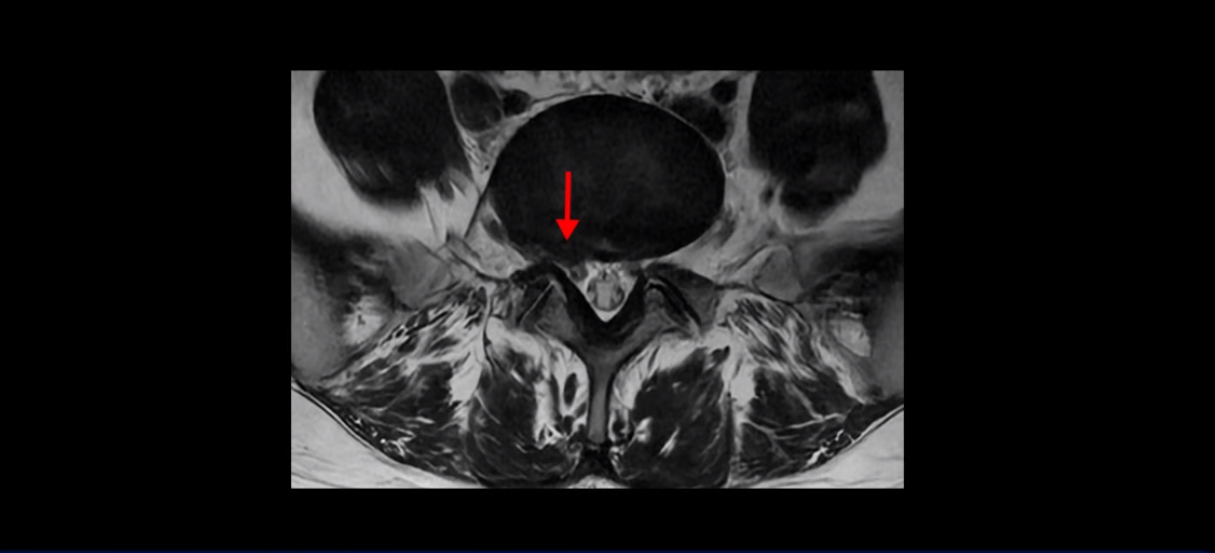

4번 5번과 3번 4번 마디도 디스크가 중앙으로 살짝 밀려나와있지만 최근에 섬유륜이 찢어진 것도 아니고, 신경 다발을 누를 정도로 심하게 밀려나와 있는 것도 전혀 아닙니다.

양쪽 신경 가지가 빠져나가는 추간공도 충분히 넓어서 신경학적 방사통을 일으킬 여지가 없습니다.

그럼 이 환자분의 양쪽 다리 저림과 발 저림 그리고 앉기만 하면 5분 내로 심한 허리 통증, 엉덩이 통증이 발생하는 원인은 뭘까요? 저희가 이런 디스크 내장증 얘기를 들으신 환자분들 치료 후기에서 수없이 설명하지만, 이런 증상이 디스크가 원인이 아닙니다. 이분도 여러 병원에서 증상과 MRI가 일치하지 않는다고 들으셨는데요.